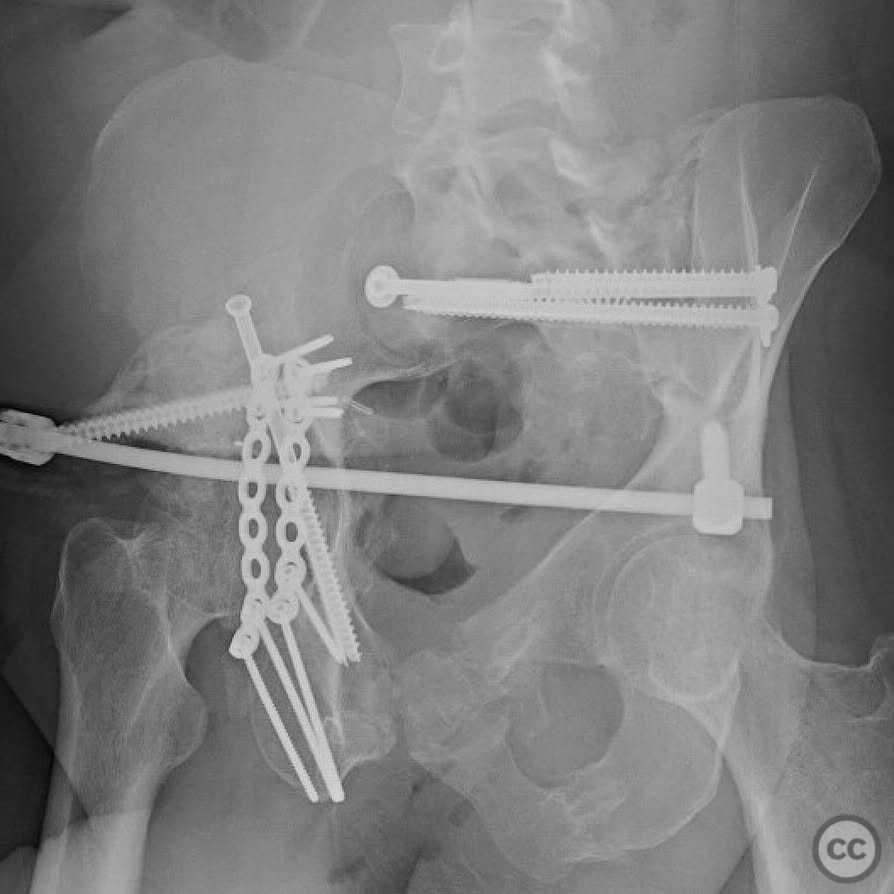

Clinical and radiological findings:  The patient presented with a highly unstable pelvic ring injury and a transverse acetabulum fracture, accompanied by a bladder injury. The bladder injury was addressed emergently with a low vertical midline Pfannenstiel incision for repair, followed by the placement of a low right-sided suprapubic catheter. Radiological imaging confirmed the transverse acetabular fracture and disruption of the left sacroiliac joint, along with a displaced sacral fracture.

Planning remarks:  The preoperative plan involved a staged approach to address the combined injuries. Initially, the focus was on stabilizing the pelvic ring to provide a stable base for subsequent acetabular reconstruction. The left sacroiliac joint disruption was to be reduced and stabilized first, followed by lag screw fixation of the displaced sacral fracture. Additional screws were planned as anatomical corridors allowed. An external fixator was considered to support the posterior ring stabilization. The second stage involved open reduction and internal fixation (ORIF) of the acetabulum through a Kocher-Langenbeck approach, with potential anterior column fixation via the modified Stoppa approach if necessary.

Orthopaedic implants used:   Lag screws for sacroiliac joint and sacral fracture fixation, external fixator for posterior ring stabilization, potential plate and screw constructs for acetabular ORIF through Kocher-Langenbeck and modified Stoppa approaches.